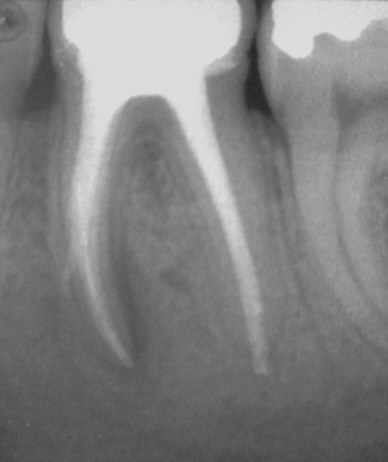

Röntgenologisch eine astreine WF in 2 Sitzungen (Mikroskop, NaOCl, CaOH2, Laterale Kondensation, sofortiger dichter Verschluss mit einer Krone ). Nachdem der Prozess unter kirschgroßer, druckdolenter Auftreibung des vestibulären Knochens im Juni 2002, also ca. 9 Monate nach WF, exacerbierte, erklärte der behandelnde Zahnarzt, die WF müsse (unter Zerstörung der Krone) revidiert werden, weil sich an der Wurzelspitze eine Entzündung gebildet habe.

Diese Aussage kann nach den vorliegenden Bildern eindeutlich als falsch identifiziert werden. Offensichtlich ist nämlich, dass dieser Prozess keineswegs neu entstanden ist, sondern dass es sich vielmehr um die Ausweitung einer entzündlichen Veränderung im periapikalen Bereich der mesialen Wurzel handelt, der bereits im September 2000 bestand. Offensichtlich ist ferner, dass das Beschwerdebild anlässlich der Erstversorgung zwar zunächst coupiert werden und in der Folge für eine gewisse Zeit Beschwerdefreiheit erzeugt werden konnte, dass er aber in keinem Fall ausgeheilt war. Die klinische Symptomatik hat also in diesem Fall eindeutig falsche Signale geliefert.

Wie man an diesem Falle sieht, heilt die Ausheilung sogar dann aus, wenn die Revision nur unvollständig gelingt und es aufgrund des überaus dichten Verschlusses durch laterale Kondensation zu einer Instrumentenfraktur und einr via falsa kommt. Wir führen diesen Umstand auf die hohe Penetrationsfähigkeit von CHMK zurück und auf die damit verbundene Tatsache, dass es bereits wenige Stunden nach Einlage in den Wurzelkanal auf der Wurzeloberfläche und damit in der Aufhellung nachzuweisen ist.